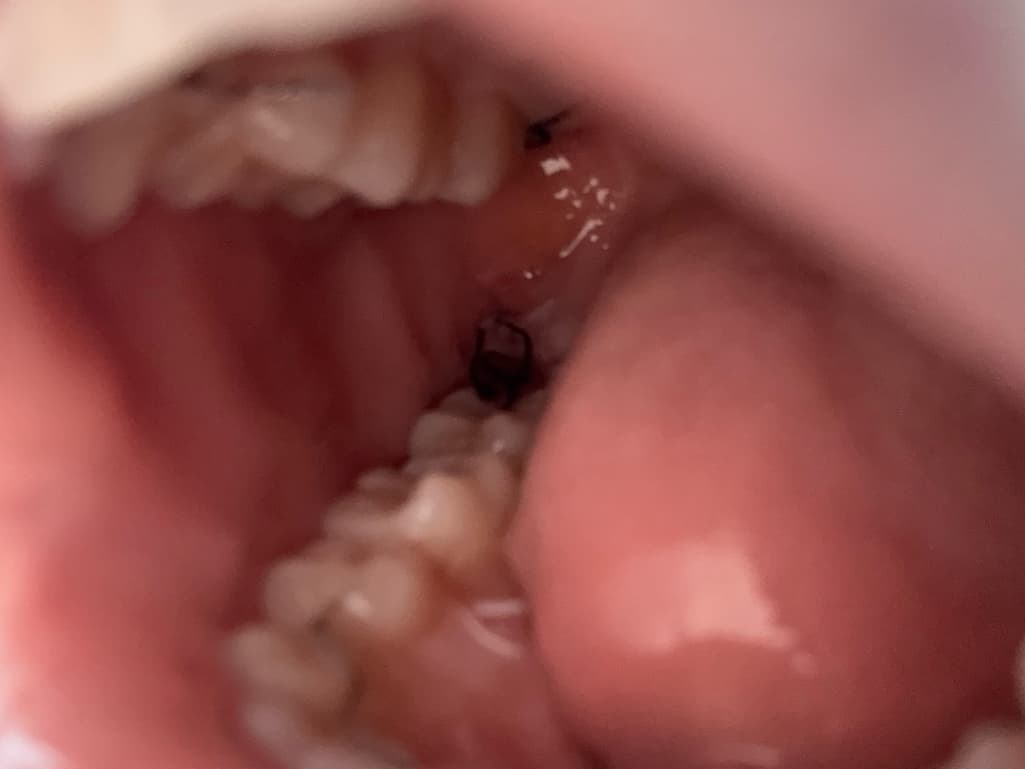

통증은 타이레놀+처방약 먹으면 잡히긴 하지만 아직 볼에 붓기는 남아 있습니다 ㅠㅠ… 다른 분들 사진 보니 보통 4일차에는 살이 조금씩 차는 것 같던데 저는 피떡이 져있어 염증일까 여쭤보고 싶습니다… 잘 회복 중인 거 맞을까요??

사진상으로 잘 회복되고 잇는거 같습니다. 사랑니 발치를 하고나서 잇몸이 아무는데는 최소 한달정도 시간이 소요됩니다.

4일차에 잇몸 바깥 부분이 조금 덮일 순 있는데 살이 차오르는 건 아닙니다. 안쪽에서 잇몸과 잇몸뼈가 차오르기 위해서는 1~2달은 기다려야 합니다.

사진상 크게 치유에 문제가 있어보이진 않습니다.